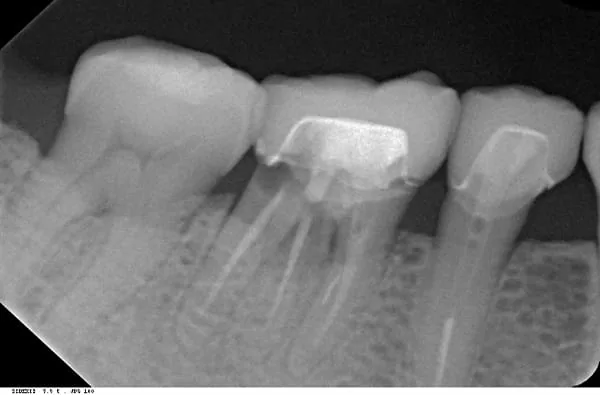

記得那天看診---醫師經由臨床上X光片仔細檢查後,發現我的這顆牙已經有牙周病的破壞,並且在牙齦下面的牙根也有蛀牙。

我同意拆掉舊有的牙套後發現 : 不只是蛀牙,而且已經蛀蝕太深,齒質已經鬆軟,無法再製作一個新的牙套。

為精確的診斷,還幫我拍攝3D斷層掃描後,確定它真的無法使用了,只能忍痛決定拔牙後再植牙。

X光片顯示已有牙周病及牙根蛀牙~汗( ̄口 ̄)!!